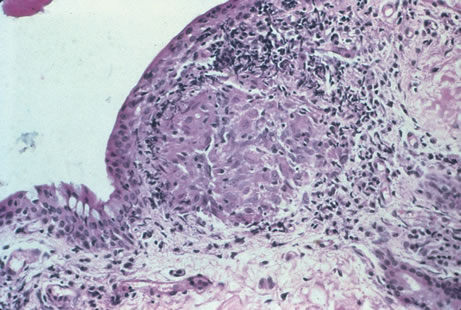

Any cell type may be infected, appearing larger than normal (cytomegalic) and demonstrating eosinophilic intranuclear “owl's eye” and smaller intracytoplasmic viral inclusion bodies, which are better seen with Giemsa or Papanicolaou's stains (Fig. 8). Histologic examination of tissue specimens, including bronchoalveolar lavage fluid and urine, may be useful for diagnosis.

|